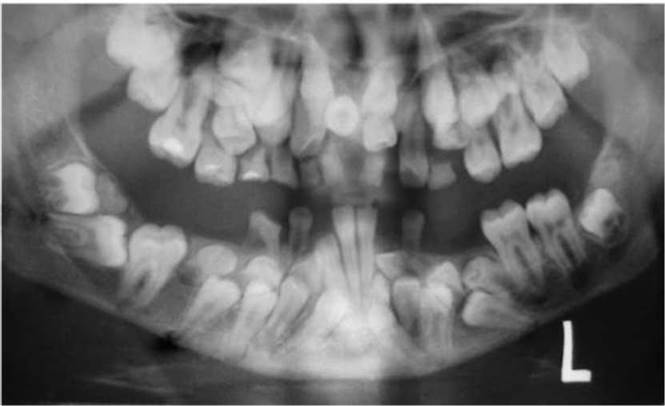

У человека возможны атавистические аномалии зубной системы, связанные с нарушениями как дифференцировки зубов, так и с их числом. Редкая аномалия - гомодонтная зубная система, в которой все зубы имеют коническую форму. Более часто встречается такая патология, как трехбугорчатое строение коренных зубов. Нередко встречается прорезывание сверхкомплектных зубов в ряду или за его пределами, иногда даже на твердом нёбе (рис. 14.23). Это свидетельствует о том, что у человека возможно образование большего числа зубных зачатков, чем 32, как это в норме встречается у низших млекопитающих и представителей более отдаленных классов позвоночных. Свидетельство тенденции к дальнейшему уменьшению числа зубов у человека - то, что нередко последние коренные зубы, так называемые «зубы мудрости», вообще не прорезываются, а если и прорезываются, то это происходит поздно - до 25 лет. Кроме того, эти зубы имеют явно рудиментарный характер, уменьшены в размерах и часто слабо дифференцированы.

Рис. 14.23. Прорезывание сверхкомплектных зубов при клейдокраниальной дисплазии